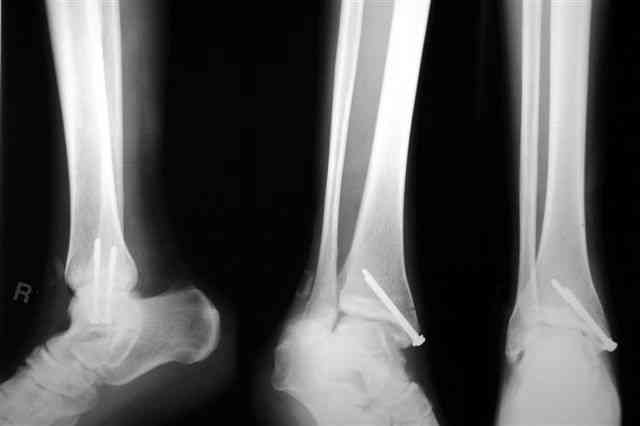

Лодыжку так ипрооперировал двумя 3.5 мм шурупами пришлось открыть - закрыто не удалось адекватно отрепонировать, при открытии - надкостничная

интерпозиция.

Бедро фиксировал длинной DCS.

В приложении отправляю послеопер. снимки бедра и лодыжки обсуждаемого вчера больного.